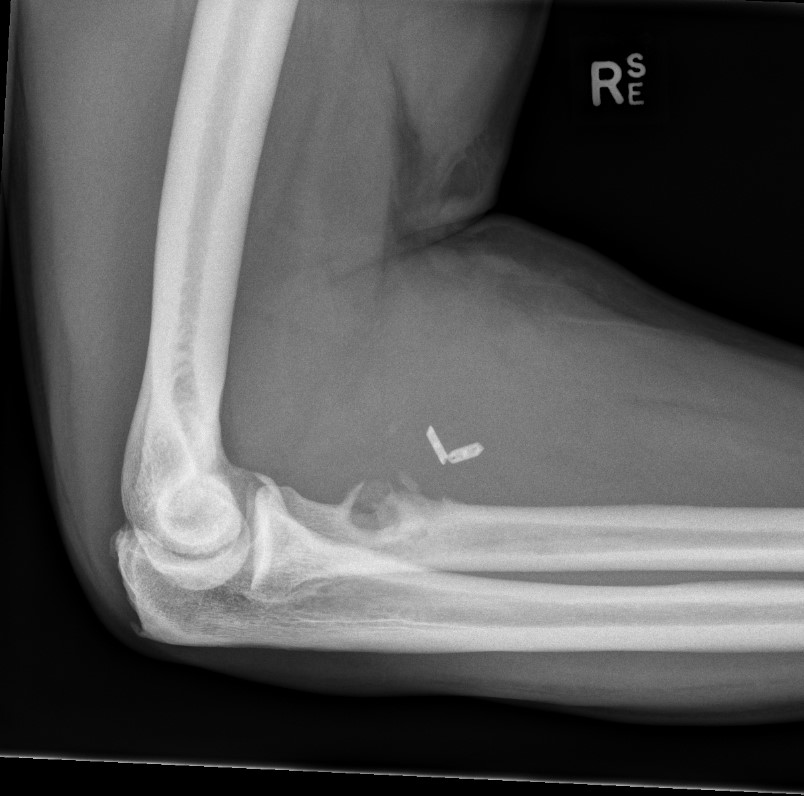

MRI

Confirm diagnosis

A.  Complete tear / retracted

Best seen on sagittal MRI

Distal biceps rupture MRIDistal biceps rupture MRI

Sagittal MRI - distal biceps retracted into arm

Distal Biceps Rupture MRI